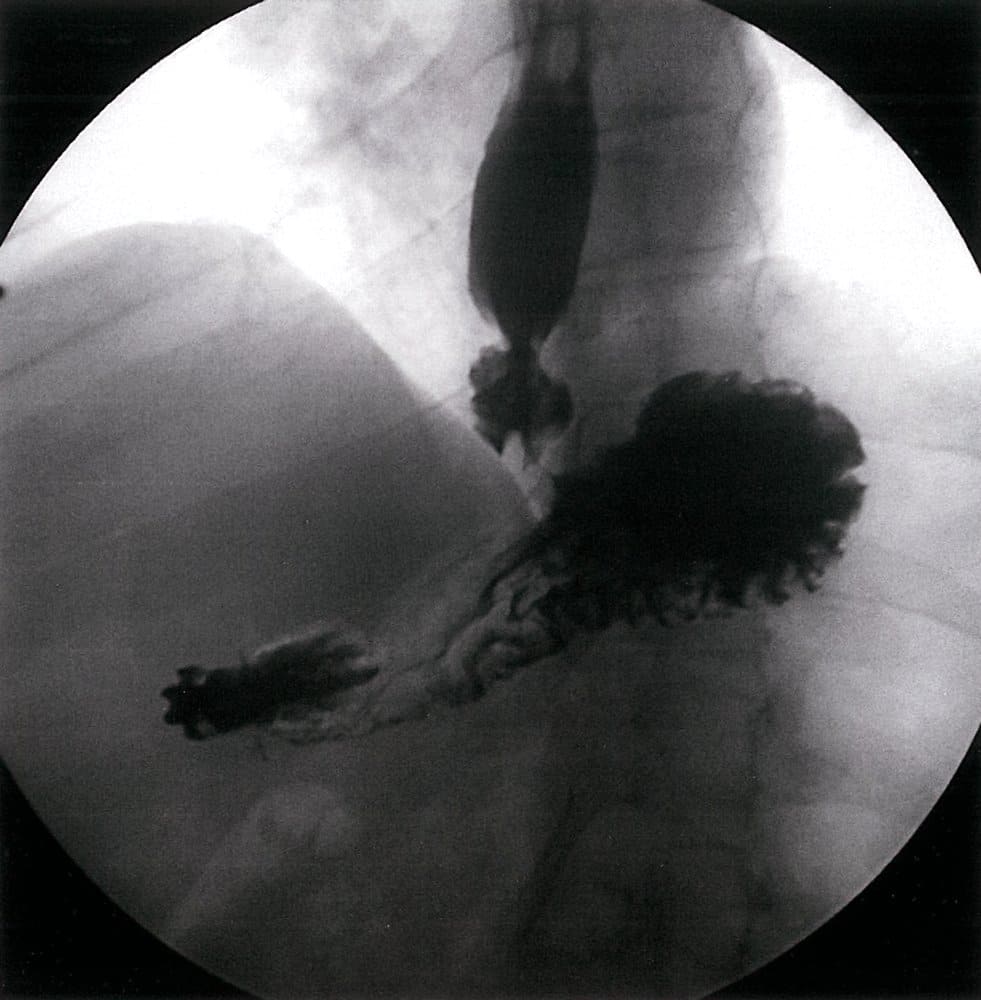

فتق هیاتال

فتق (هرنی) هیاتال به بیرونزدگی غیرطبیعی ارگانهای شکمی از جمله معده (شایعتر) یا رودهها به داخل قفسه سینه از طریق سوراخ عبوری مری در دیافراگم گفته میشود. این عارضه میتواند مادرزادی و یا اکتسابی باشد، از ریسک فاکتورهای فتق هیاتال اکتسابی میتوان به سیگار، چاقی و افزایش سن اشاره کرد. میتوان انواع آن را به چهار دسته تقسیم کرد: Sliding (لغزشی)، پاراازوفازیال، مختلط و کمپلکس.